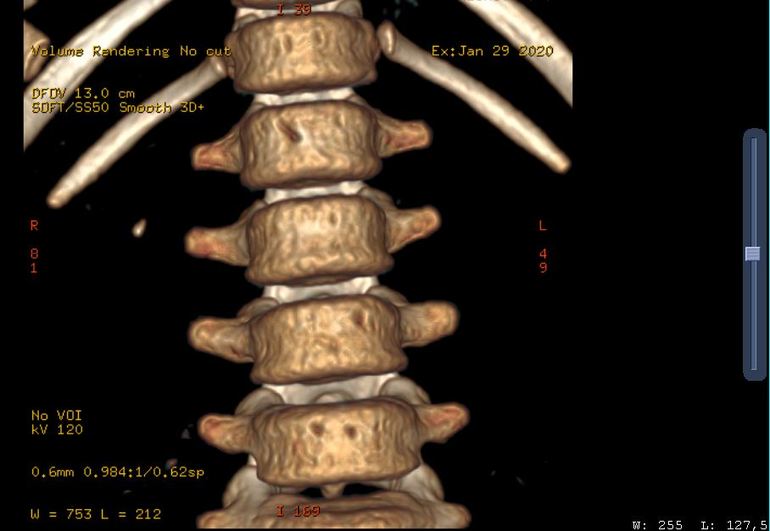

Получилось открыть диск с КТ, вот нашла что-то вроде напоминающее камень.

Хороший конкремент, такой будет видно на УЗИ. При цистоскопии никаких источников гематурии на слизистой не нашли? В чем была выражена макрогематурия, сгустки, равномерное окрашивание?

Здравствуйте. Мне сложно объективно судить о вашей ситуации, поскольку я не видел первоисточников клинической информации. Любые по составу конкременты почки, размерами более 3-4 мм, хорошо видны при УЗИ. Наличие единичного конкремента 3-4 мм, не является обязательной причиной гематурии. Мне кажется в вашей ситуации не все так однозначно.